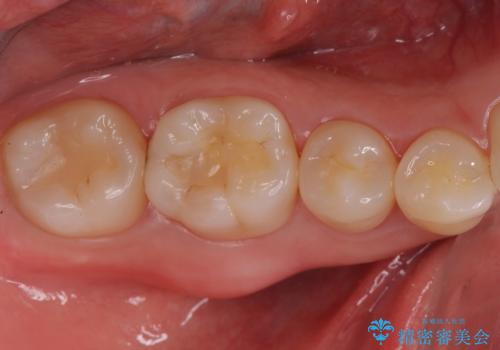

激しく痛む奥歯を治したい

目立つ銀歯を白くしたい ジルコニアクラウンでの修復

担当医 岡田康成